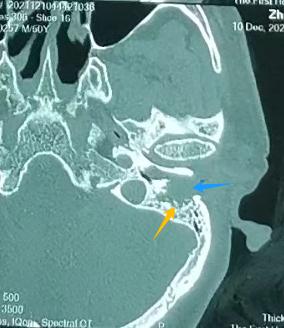

左耳:外耳道有肿物(左图)

对比右耳:外耳道通畅,鼓膜完整(右图)

张宏征发现,周先生左外耳道长了淡红色肿物,结合他长期的掏耳习惯,怀疑很可能是外耳道癌,立即为他进行外耳道肿物病理检查,结果证实周先生患的是罕见的 “左外耳道鳞状细胞癌”。